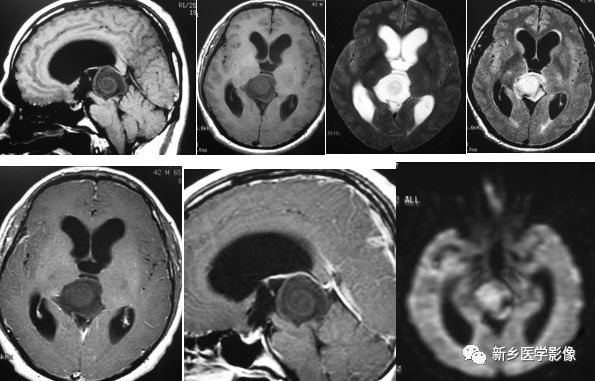

(WHO分级中属于II~III级)

中分化松果体实质肿瘤为富核肿瘤。其可表现为轻度核不典型增生,偶尔可有核分裂。松果体细胞瘤玫瑰花结构缺失。与松果体母细胞瘤不同,中分化松果体实质肿瘤转移不常见。

横断位T1WI示松果体区高信号肿块,T2WI呈高信号,T21WI+FLAIR呈高信号,T1WI+C示部分强化。

松果体母细胞瘤

松果体母细胞瘤在男性及女性的发病率均等,主要见于10-20岁人群。其发病率约为松果体瘤的6倍。双侧视网膜母细胞瘤合并松果体母细胞瘤被称为三侧视网膜母细胞瘤。松果体母细胞瘤内可出现钙化。在磁共振上,其表现为T1WI低信号及T2WI高信号。病灶可见强化。

12岁儿童,矢状位T1WI示松果体区低信号肿块,横断位T2WI示一高信号肿块右份伴局灶性低信号,代表钙化,注意与病灶相关的脑积水;横断位及矢状位T1WI+C示明显强化肿块。

松果体细胞瘤

松果体细胞瘤男女发病比率相当。它可以发生于任何年龄组,但是患松果体细胞瘤患者通常比松果体母细胞瘤患者年龄大。在T1WI上其表现为等-高信号,T2WI表现为高信号。增强可见强化,肿瘤内可出现钙化。